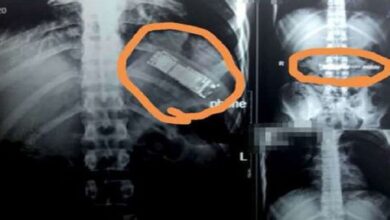

Phone Swallowed: छापेमारी के दौरान कैदी ने निगला फोन

पटना: बिहार के गोपाल